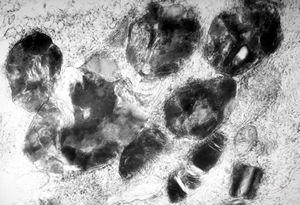

F, 24y. | molluscum contagiosum … virions

F, 24y. | molluscum contagiosum

F, 24y. | molluscum contagiosum

F, 7y. | molluscum contagiosum … virions

F, 7y. | molluscum contagiosum … virions

F, 24y. | molluscum contagiosum … virions